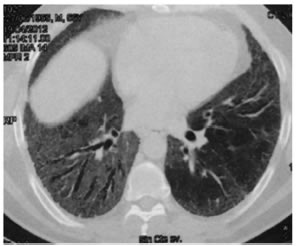

Al examen físico inicial, presentaba saturación de oxígeno (SatO2) de 93% a aire ambiente, dedos en palillos de tambor y rales tipo velcro en ambos campos pulmonares. Los análisis de laboratorio realizados: Látex AR, colagenograma, HIV y TBC fueron negativos. La espirometría mostró valores dentro de la normalidad, FVC 3,56 lts (83%); FEV13,11 lts. (91%); FEV1/FVC 87%. La TCAR de tórax mostró atenuación en vidrio esmerilado bilateral a predominio en lóbulos inferiores, periférica, subpleural y engrosamiento reticular interlobulillar, con presencia de bronquiectasias por tracción en lóbulo inferior derecho; sin descripción de adenopatías, enfisema ni panalización. Tampoco se encontró afección pleural (Figuras 1 y 2). El test de marcha de 6 minutos (TM6M) demostró una limitación severa de su capacidad funcional, debió ser finalizado en el 2° minuto por desaturación a 80% (FiO221%) tras haber recorrido 165 mts. Se decidió realizar una biopsia por videotoracoscopia; el reporte histológico fue fibrosis septal con macrófagos intraalveolares de características homogéneas de aspecto descamativo. Los patólogos concluyeron en el diagnóstico de neumonía intersticial descamativa (NID), sin presencia de patrón de neumonía intersticial usual (NIU) ni neumonía intersticial no específica (NINE). Se inició un curso de meprednisola 1 mg/kg/día y se prescribió oxigenoterapia.